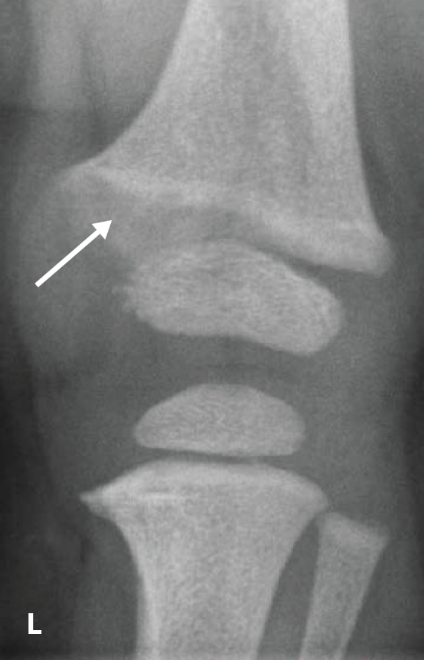

The RSS is a quantitative method that uses radiographs to assess the severity of rickets at the wrists and knees. Originally validated in nutritional rickets, the score is based on the degree of metaphyseal fraying, metaphyseal cupping, and the proportion of the growth plate that is affected. It is a 10-point scale, for which 10 represents the most severe radiographic changes due to rickets and 0 represents the absence of these changes.1

Although the severity and duration of rickets vary considerably between XLH and nutritional rickets, the radiographic features of rickets at the growth plate are similar in the two disorders, which allowed validation of the RSS in XLH. The RSS correlates with serum alkaline phosphatase (ALP) levels, a biochemical marker of rachitic activity, and this scoring system can be used to assess the radiographic response following treatment of nutritional or XLH rickets.

The RSS in XLH has been reported to range from 0 to 4.5; however, despite the smaller RSS range observed in XLH patients, inter- and intra-rater reliability are similar to those reported for nutritional rickets. Patients with XLH who had a baseline RSS ≥1.5 were shown to have more severe hypophosphatemic bone disease, including higher levels of alkaline phosphatase, and greater impairments in clinical outcomes compared with patients who had a baseline RSS <1.5.